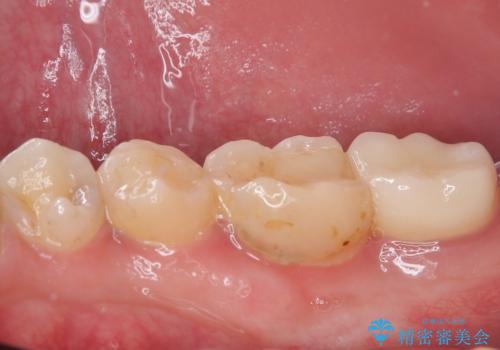

- 右下の奥歯が大きく欠けてしまったのを治したいと来院された患者様です。

舌側の歯冠がなくなってしまっていて、健全な歯質が歯茎の下にある状態です。

このままの状態だと土台がたてられず被せものがいれられないため、歯肉の切除と歯槽骨の形態修正を行い、歯の健全な部分が歯肉の外に出てくるようにしたうえで、オールセラミッククラウンによる補綴治療を行うこととしました。

根管治療のやり替えも提案しましたが、希望されなかったため行いませんでした。